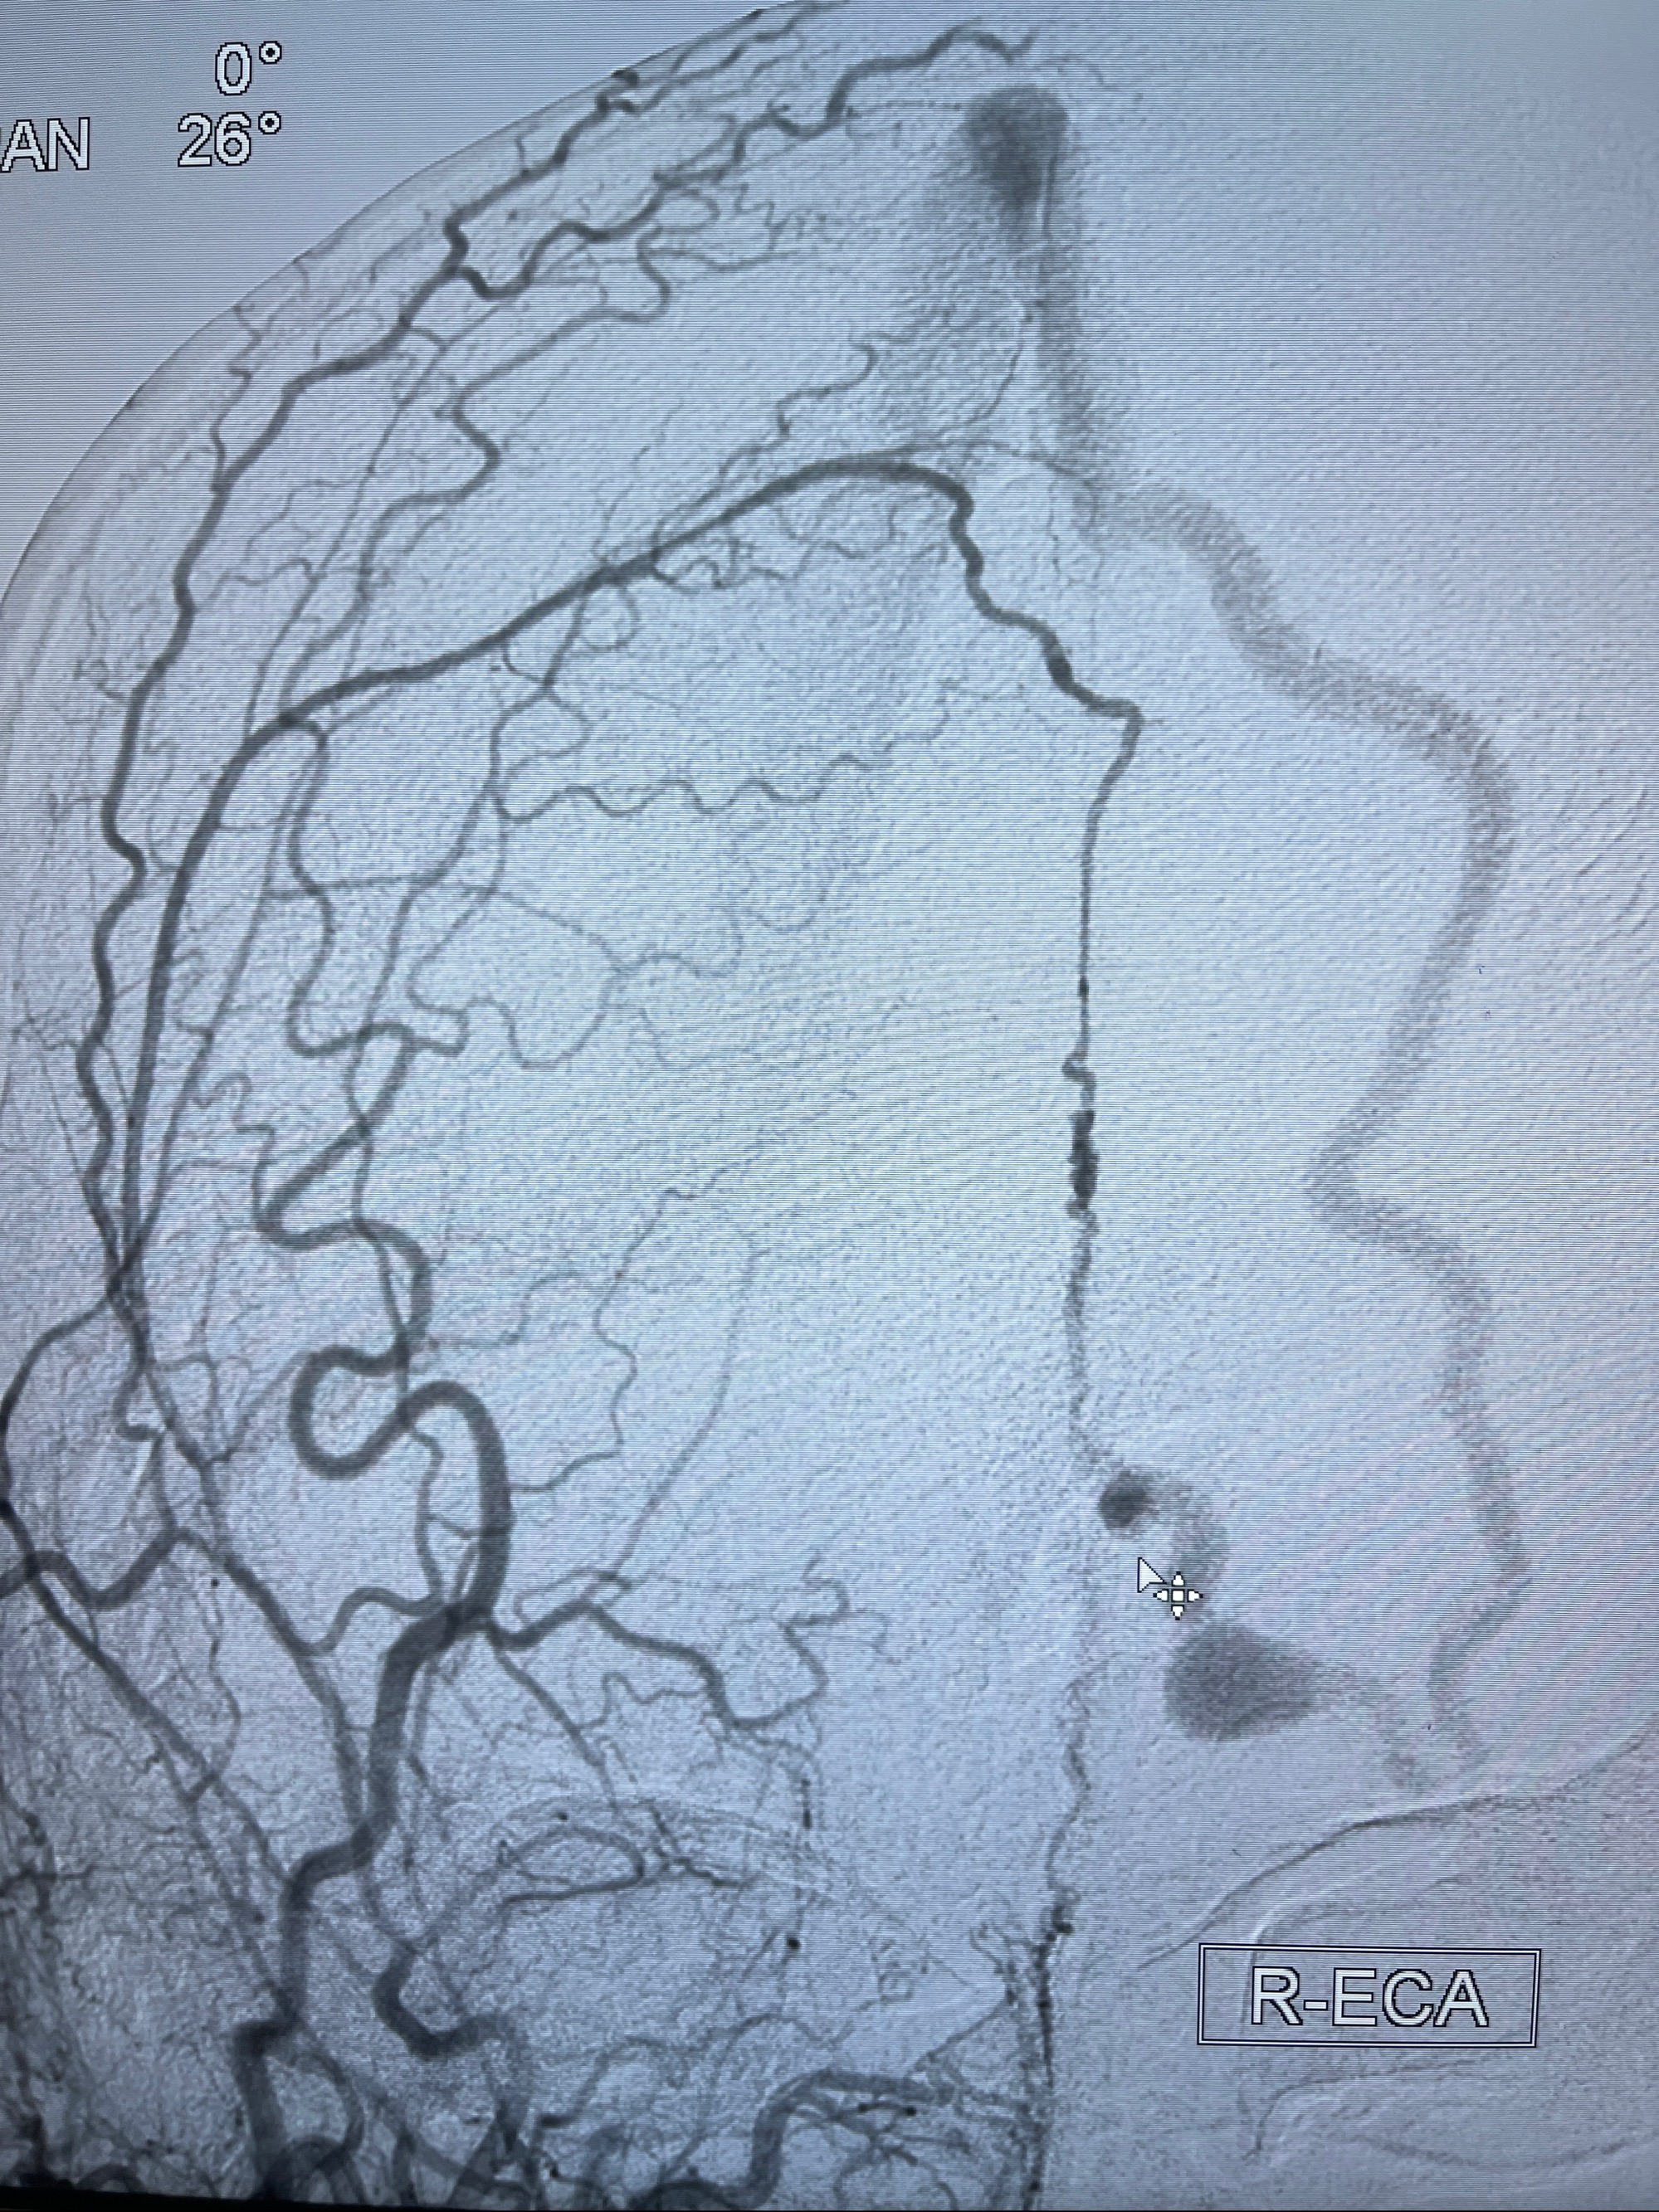

2023年8月21日]景德镇市第一人民医院脑血管造影检查,提示:主动脉弓、双侧颈总动脉、锁骨下动脉造影未见异常,左侧大脑前动脉静脉瘘。

2023-09-13全脑血管造影:前颅底硬脑膜动静脉瘘,供血动脉为双侧胼周动脉、眼动脉脑膜支,静脉向上矢状窦方向引流